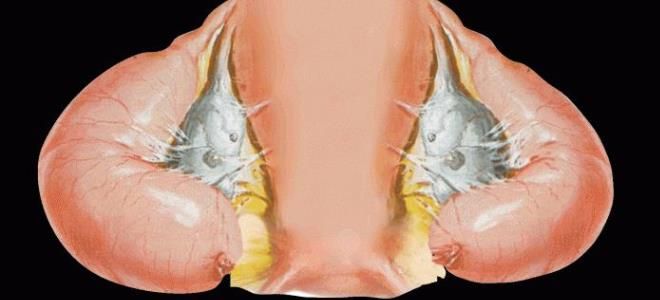

Гидросальпинкс – это патологическое состояние, при котором происходит скопление жидкости внутри фаллопиевой трубы. Cкопление вызвано блокировкой или закупоркой фимбриального конца трубы, то есть есть ее наружной части, которая связана с яичниками. Такая блокировка часто является следствием воспалительного процесса в трубах, что может привести к их повреждению и последующему функциональному нарушению.

Фаллопиева труба, имеет круглого сечения и соединяет матку с брюшной полостью. Один ее конец прямо связан с маточной полостью, в то время как другой, фимбриальный конец, открыт в брюшную полость. Внутри пространство трубы выстлано оболочкой, состоящей из железных клеток, которые вырабатывают слизь. В нормальном состоянии, когда фаллопиева труба не заблокирована, слизь и яйцеклетка могут свободно перемещаться к матке, в этом процессе играют ключевую роль реснички — микроскопические структуры на клетках, обеспечивающие направленное движение внутри трубы.

Скопление жидкости в фаллопиевых трубах вызывает механическое давление на стенки, что ведет к их истончению и приводит к функциональным нарушениям. Обычно, фаллопиева труба служит местом для оплодотворения яйцеклетки, которая затем, благодаря движению ресничек, перемещается в матку для имплантации в эндометрий. Однако при гидросальпинксе этот процесс нарушается, что часто приводит к развитию трубно-перитонеального бесплодия. Степень тяжести заболевания зависит не только от состояния внутри трубы, но и от того, есть ли давление на нее извне, например, из-за образования спаек в брюшине.